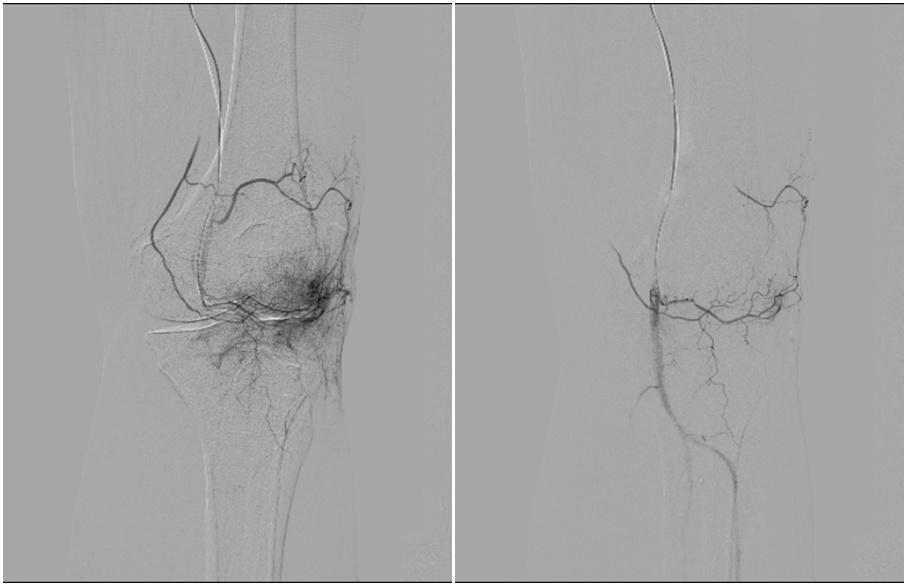

“我们通过在患者大腿根部的微小穿刺点,将导管送至膝关节的病变血管处。”朱永强指着显示屏上的影像说,病变血管网络在影像下会呈现为异常染色的“云雾状”区域,这些就是炎症的根源。他们通过栓塞精准切断异常血管的血供,从源头消除炎症。

术前左膝关节造影可见异常染色(左图)栓塞后异常染色消失(右图)

“与传统治疗相比,关节动脉栓塞术优势在于,可以从源头上通过血管途径消除炎症,从而达到‘治本’目的。”朱永强表示,该治疗方式的费用远低于关节置换手术。更重要的是,这个技术可以重复进行,为患者保留了后续治疗的选择。